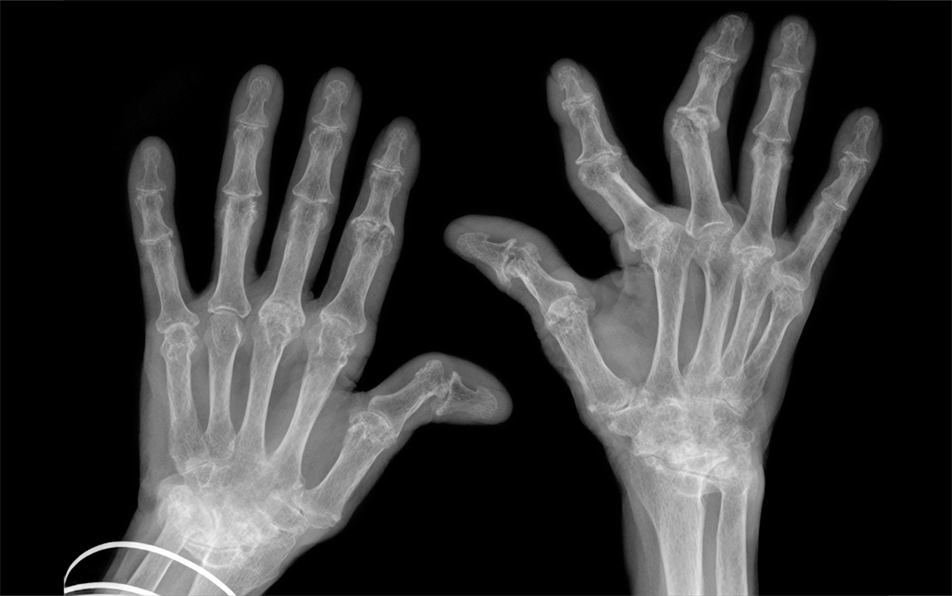

Arthritis Drug Baricitinib . It’s a type of drug known as a janus kinase (jak) inhibitor. Baricitinib is a biological dmard that can be used with or without methotrexate for severe active rheumatoid arthritis. Baricitinib, also known as olumiant, is used to treat rheumatoid arthritis. Baricitinib is a jak inhibitor used to treat rheumatoid arthritis, atopic eczema and alopecia areata. Learn about its brand names, interactions,. It has important safety warnings and.